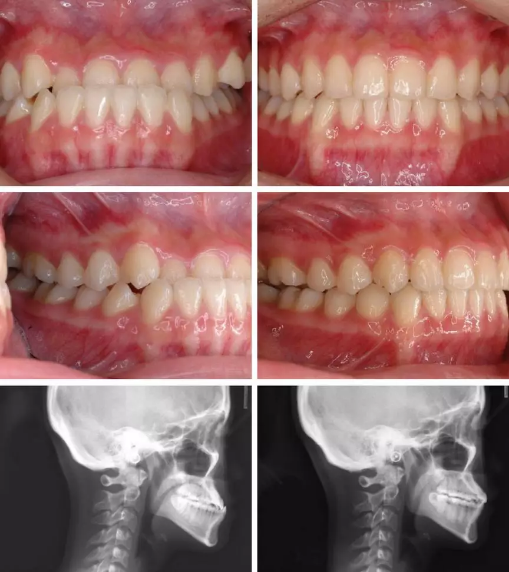

CASE 4

关键词

地包天、牙齿拥挤、拔牙

其实我们做过很多地包天的案例都没有拔牙的~

也有少数cases是比较严重的地包天,需要拔掉下排两颗牙齿把下排推进去很多。比如上面这个姑娘。

这个变化是相当大了!时间也比较久,65幅牙套,21个月

幅 65 21 月

CASE 5

过咬合、凸嘴

这个弟弟虎牙非常的调皮,下牙也歪。这个case没有拔牙,因为上下差不大,总共是59个牙套,时长18个月,虎牙严重的移位,要让这颗牙回来时间就比较长,如果只是简单排列不齐,那一般一年之内可以搞定。

幅 59 18 月